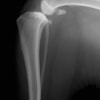

バーニーズマウンテンドック 4歳 避妊♀

突然の右後肢跛行を主訴に来院されました。整形外科学的検査において右膝に脛骨圧迫テストで陽性、前方引き出し徴候が認められました。神経学的検査において特に異常は認められませんでした。レントゲン検査において、関節液の貯留所見や脛骨の前方変位の所見が認められました。

断裂前十字靭帯の除去を行いました。その後 TTA(Tibial tuberosity advancement)を実施しました。

術後経過は良好で、後肢機能・筋肉量の改善目的で現在はリハビリテーションを行っています。